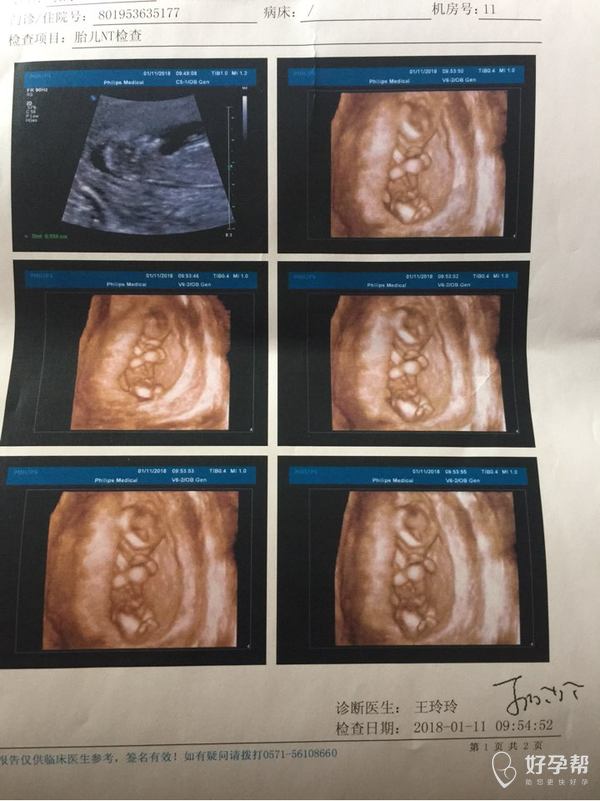

医生帮忙看看,今天12周加4做的Nt